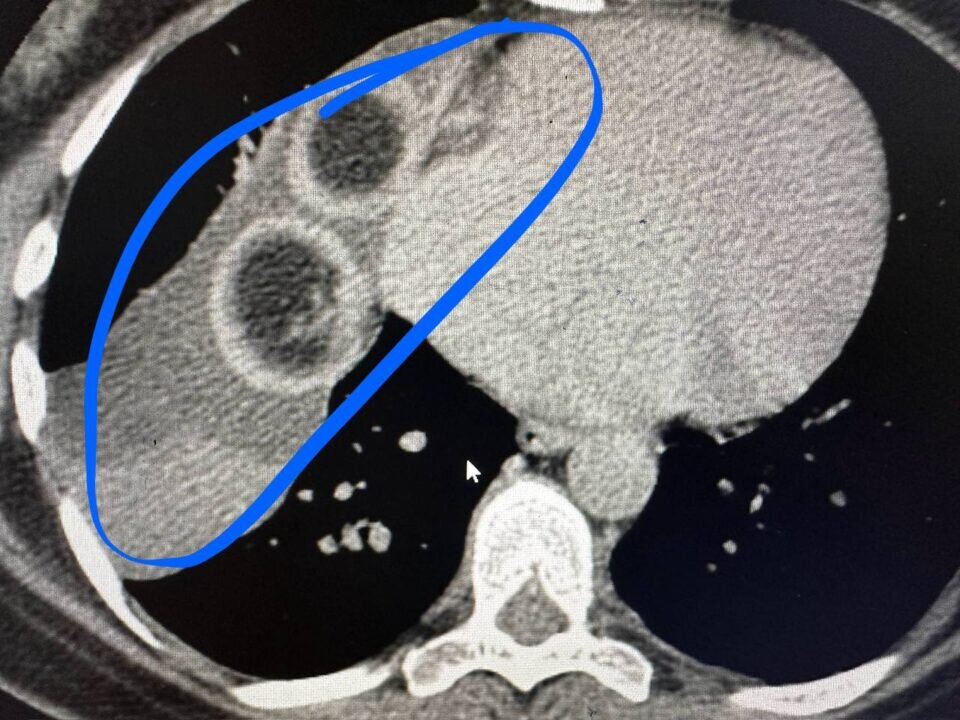

Операция была сделана через три прокола и продлилась два часа. Врачи РКБ Татарстана удалили у пациентки большую дермоидную кисту с клубками волос внутри, рассказали в пресс-службе клиники.

Образование обнаружили у 44-летней жительницы Бавлов, когда делали флюорографию. Женщину сразу же направили на КТ. Исследование подтвердили наличие кисты.

Выяснилось, что образование появилось совсем рядом с сердцем. Киста была внушительных размеров — 10 на 7 и на 15 сантиметров. А внутри кисты — два больших клубка волос. Ранее KazanFirst писал, что в Казани впервые провели операцию с пересадкой донорской почки подростку.

Врачи РКБ Татарстана удалили у пациентки большую дермоидную кисту с клубками волос внутри, рассказали в пресс-службе клиники.

Выяснилось, что образование появилось совсем рядом с сердцем. Киста была внушительных размеров — 10 на 7 и на 15 сантиметров. А внутри кисты — два больших клубка волос.

• Образование удалили торакоскопически — через 3 прокола. Операция длилась два часа. Уже через несколько часов после хирургического вмешательства пациента ходила по палате.